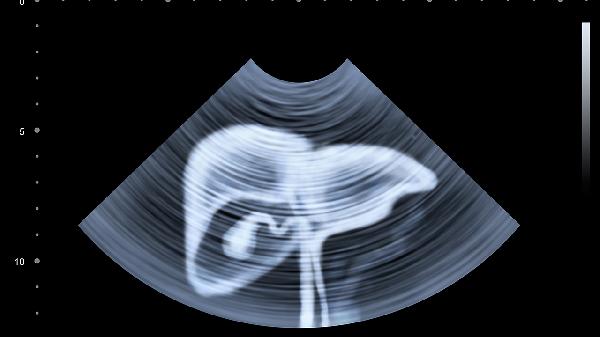

如果是做卵巢切除的手术,这个对于怀孕方面是有一定的影响的,如果只是单纯的取出囊肿,不损伤卵巢功能,对于生育方面影响并不大,这个是需要看手术的类型的,也需要看囊肿的性质以及是否存在其他疾病。对于患者的情况,可以去附近的门诊或者医院请医生检查后听取医生的建议